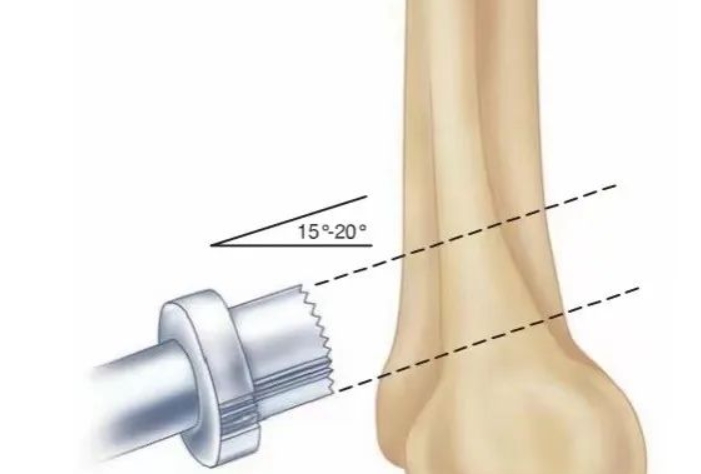

肘关节镜下Outerbridge-Kashiwagi手术